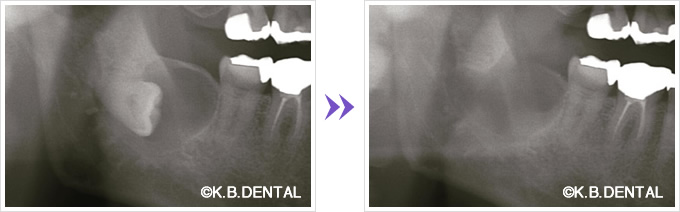

歯牙腫(しがしゅ)

歯牙腫摘出 症例1

歯牙腫摘出の症例です。歯の腫瘍のようなもので、当院では良性腫瘍のケースを主に除去しています。成人の若い方に多く、症状や主訴としては、お口の違和感や歯ぐきの腫れ、歯と似たようなものが歯ぐきから飛び出してきたり等です。ピエゾサージェリーを使用し、口蓋アプローチで周囲の歯牙は抜髄せず、腫瘍のみ丁寧に摘出したケースです。

料金

静脈内鎮静法による麻酔代込み:約15~20万円(保険適用外)

歯牙腫摘出 症例2+埋伏歯(まいふくし)

歯牙腫摘出と埋伏歯抜歯のコンビネーション症例です。お口の違和感で来院された20代女性の方です。抜歯、摘出はピエゾサージェリーを併用するので周囲の歯にダメージを与えず摘出可能、低侵襲に行えます。

通院回数事前検査から手術~抜糸~消毒などを含めて5回、治療期間は約1ヶ月でした。静脈内鎮静法による無痛リラクゼーション麻酔を行い、無痛下で行いました。